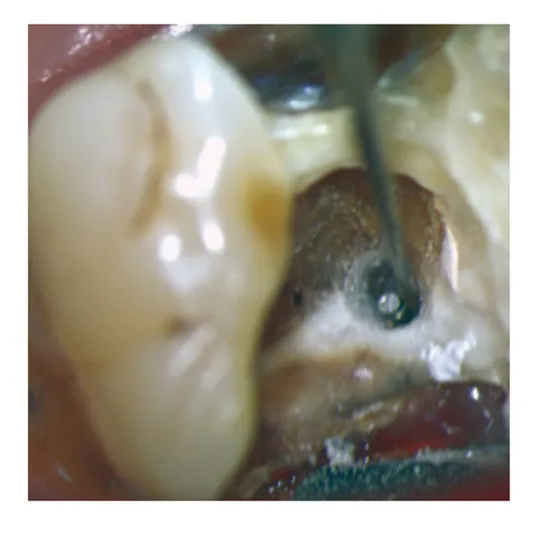

牙醫師會使用特殊工具擴大根管系統,然後使用藥水清除根管內發炎或壞死的牙髓組織,以及任何可能存在的細菌。這樣可以減少感染源及細菌在根管內的生長,增加治療的成功率。對於較為複雜的根管治療,有些牙醫師會使用高階顯微鏡輔助,徹底消除根管內的感染源。

清除感染組織